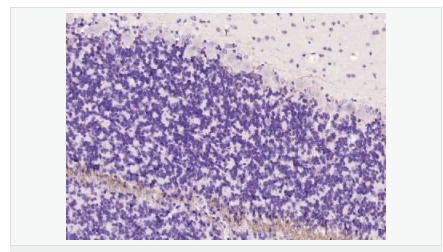

少突膠質(zhì)細(xì)胞標(biāo)志物

主要用于脊髓脫髓鞘病-脊髓多發(fā)硬化癥的研究。

MBP髓鞘堿性蛋白和髓鞘相伴糖蛋白是多發(fā)性硬化的自身免疫攻擊的靶。

Myelin basic protein (MPB) :Oligodendrocyte Protein produced by mature oligodendrocytes; located in the myelin sheath surrounding neuronal structures 髓磷脂Myelin/oligodendrocyte specific protein (MOSP)是由中樞神經(jīng)系統(tǒng)中少突膠質(zhì)細(xì)胞和外周神經(jīng)系統(tǒng)中雪旺氏細(xì)胞產(chǎn)生特殊蛋白質(zhì)。是形成髓鞘的主要成分,對(duì)于引導(dǎo)神經(jīng)沖動(dòng)的傳遞起著致關(guān)重要的作用。 多年來,關(guān)于髓鞘的形成機(jī)理和與其相關(guān)的一些先天性疾病的發(fā)病機(jī)制一直是眾多科學(xué)家關(guān)注的重點(diǎn)。如:多重硬化癥和腦白質(zhì)營養(yǎng)不良等,都與神經(jīng)系統(tǒng)的去髓鞘化相關(guān)。